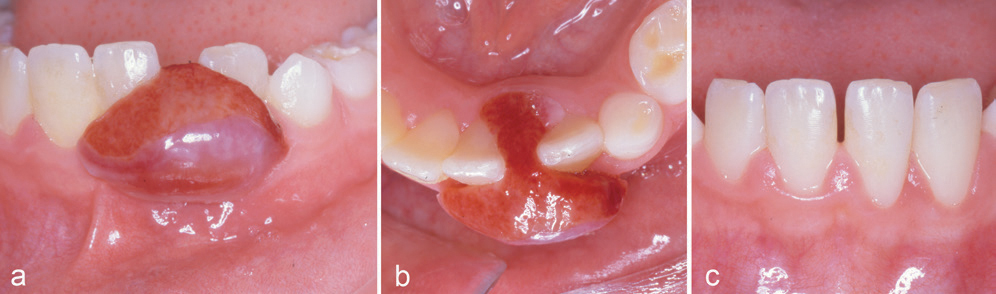

Kasus 10

En 45-årig mann var henvist fra egen tannlege for fjerning av tumor regio 47–48. Dette var et tilfeldig funn hos egen tannlege, pasienten hadde ingen subjektive symptomer. Undersøkelse viste en 30–40 mm stor tumor som vokste opp over occlusalplanet av 47 (figur 8a). Pasienten hadde en anamnese med testikkel-cancer, og av den grunn ble pyogent granulom eller metastase kliniske overveielser. Det histologiske bildet viste igjen PKCG. På grunn av hastehenvisning ble den delen av tumor som var inne i benet ikke fjernet (figur 8b). Det ble gjort to måneder senere, og diagnosen var den samme. Siden det meste av tumor lå utenfor ben, ble dette karakterisert som PKCG og ikke sentralt kjempecellegranulom. Seks måneder postoperativt var det full tilheling klinisk og røntgenologisk uten tegn til residiv (figur 8c).

Figur 8. Kasus 10. PKCG hos en 45-årig mann med nedbrytning av ben marginalt (a, b). Postoperativ kontroll 6 måneder etter fjerning av benet del av PKCG, uten tegn til residiv (c).